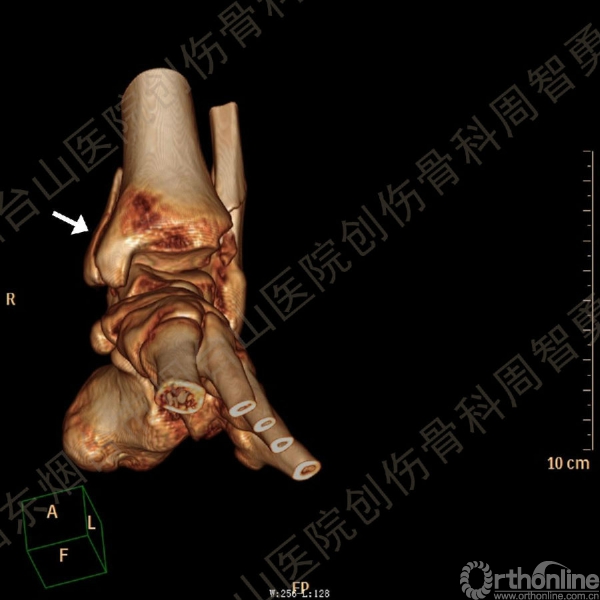

患者一般情况可,左踝关节肿胀,见皮下瘀斑,内、外、后侧有压痛,左踝关节主动运动受限,左足皮肤感觉、血供未见明显异常,左足趾各关节可主动运动。左踝关节正位X线片和CT重建示内踝内上方双层骨皮质影(图1a,c),CT示后侧骨折块分为后内侧骨折块和后外侧骨折块(图2a,b),后内侧骨折块累及内踝后丘,后丘骨折线呈冠状位(图2c),后内侧骨折块腹侧有向近端塌陷的小块骨软骨骨折块(图2d),CT也显示Chaput骨折块(图1c,2e)。

经典的后踝骨折发生于低能量旋转外力所致的踝关节骨折;标准pilon骨折见于高能量轴向暴力;而后侧pilon骨折是旋转外力和轴向暴力共同作用的结果,属于中等能量的损伤。踝关节骨折中的后踝骨折源自下胫腓后韧带的牵拉,骨折块位于后外侧,常为单一的三角形骨折块,大小从关节外片状骨折到累及胫骨远端关节面矢状径的40%(图4a)。后侧pilon骨折中的后侧骨折块较大,累及内踝后丘(三角韧带深层起点)在内的整个胫骨远端后侧,分为后内侧骨折块和后外侧骨折块,后内侧骨折块腹侧有向近端塌陷的骨软骨骨折块(图4b)。后侧pilon骨折中的内踝骨折线并不是水平位而是冠状位,可合并内踝前丘骨折。后侧pilon骨折踝关节正位X线片示特异性的内踝内上方双层骨皮质影(图1a,c)。这是由于后内侧骨折块的骨折线延伸到胫骨远端骨骺和干骺端的内侧骨皮质,其移位后的边缘成像所致。水平位CT显示后侧骨折块分为后内侧骨折块和后外侧骨折块,矢状位CT示后内侧骨折块腹侧有向近端塌陷的骨软骨骨折块。

↑图 1c

图 1 术前左踝关节正侧位X线片和CT重建,箭头所示内踝内上方双层骨皮质影(a,c)